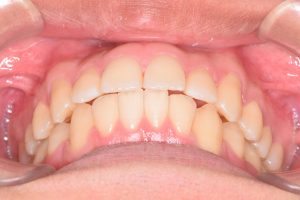

2期治療開始時(2023年7月)と装置撤去時(2025年9月)の写真です。

下から